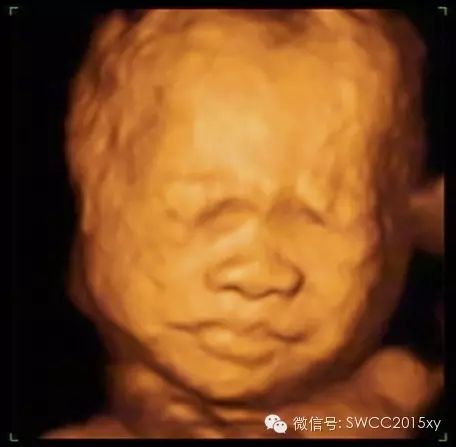

看我皱了一下眉,哦原来我是中国的宝宝,我不是西方的亚当,原来都是妈妈缺钙引起的。因此我们在判断胎儿是否缺钙,不仅仅是看胎儿的长骨的钙化程度和双顶径与股骨的比值,还可以利用现代先进的医学来判断,四维彩超的透明模式来看胎儿的肋骨发育提供更加准确、全面、科学的诊断依据,为减少先天性佝偻病做出应有的贡献。所以准妈妈一定要注意营养、规律、全程、有效补钙哦。